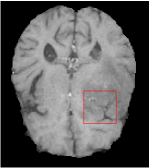

In this section, we test the generalizability of the proposed model that tests on unseen tasks. We fix the well-trained task-invariant parameter and only train for sampling ratios 15%, 25% and 35% with radio masks and sampling ratios 10%, 20%, 30% and 40% with Cartesian masks. In this experiment, we only used 100 training data for each CS ratio and apply a total of 50 epochs. The averaged evaluation values and standard deviations are listed in Table 5.4 and 5.4 for reconstructed T1 and T2 brain images respectively that proceed with radio masks, and Table 5.4 shows the qualitative performance for reconstructed T2 brain image that applied random Cartesian sampling masks. In T1 image reconstruction results, meta-learning improved 1.6921 dB in PSNR for 15% CS ratio, 1.6608 dB for 25% CS ratio, and 0.5764 dB for 35% comparing to the conventional method, which in the tendency that the level of reconstruction quality for lower CS ratios improved more than higher CS ratios. A similar trend happens in T2 reconstruction results with different sampling masks. The qualitative comparisons are illustrated in Figure 2, 4 and 5 for T1 and T2 images tested in skewed CS ratios in radio masks, and T2 images tested in Cartesian masks with regular CS ratios respectively. In the experiments that conducted with radio masks, meta-learning is superior to conventional learning especially at CS ratio 15%, one can observe that the detailed region in red boxes keeps edges and is more close to the true image, while conventional method reconstructions are hazier and lost details in some complicated tissue. The point-wise error map also indicates that Meta-learning has the ability to suppress noises.